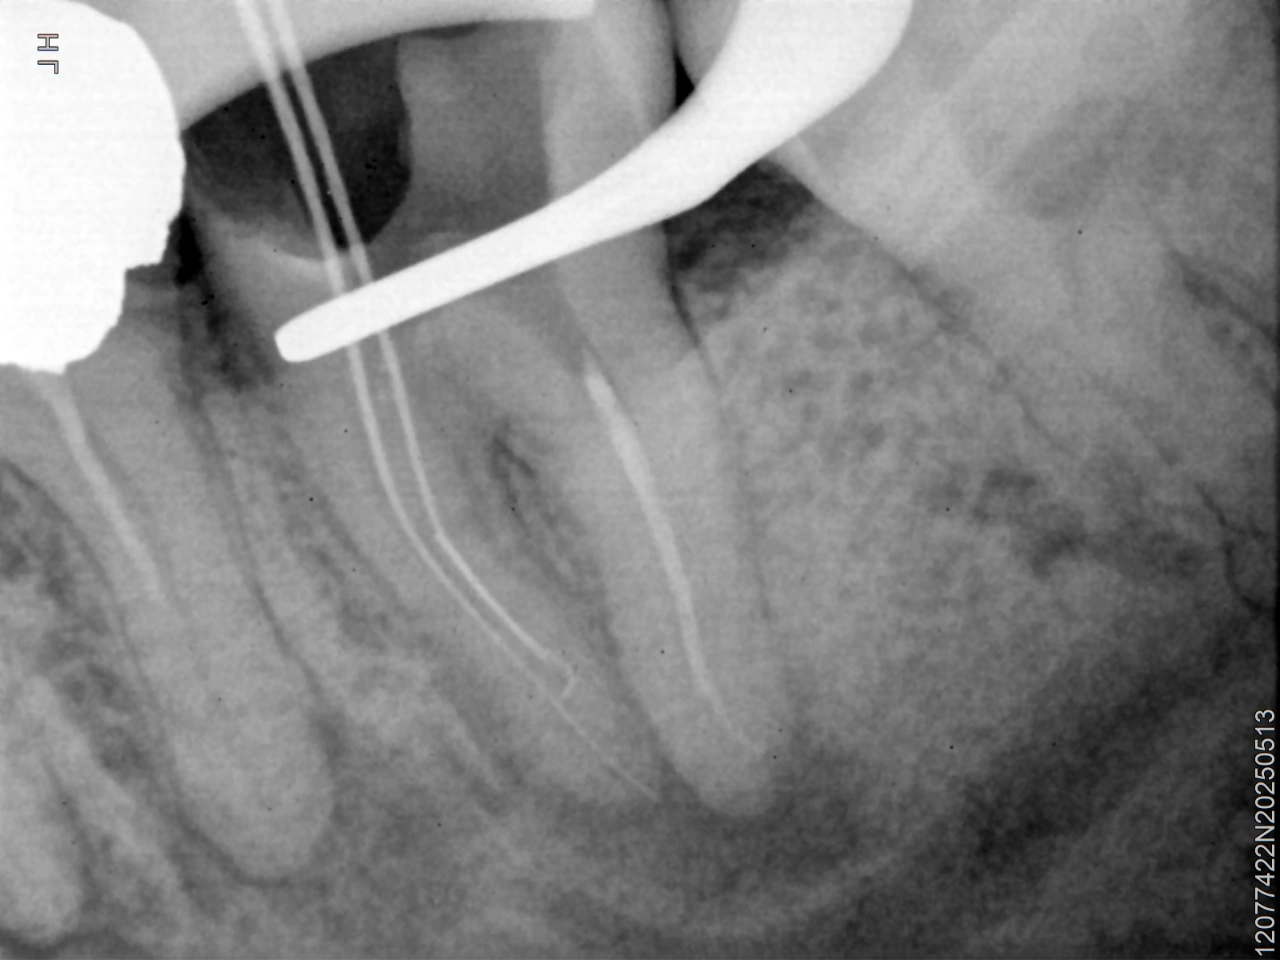

Instrument bypass radiograph

Clinical Decision: A bypass technique was selected to regain canal patency and allow adequate disinfection.

Outcome: Successful bypass and obturation were achieved, confirmed radiographically.